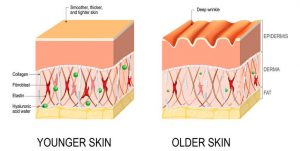

Collagen plays key roles in healthy, smooth and supple skin.

It strengthens the skin, benefit elasticity and hydration.

What happens when your body produces less collagen either due to ageing or other factors?

You look dry and dehydrated.

Your skin looses moisture and forms wrinkles.

You loose skin elasticity, firmness, radiance, and that plumpness you’re so keen to not loose.

Collagen supplements can also promote hyaluronic acid production, with its ability to stimulate dermis receptors.

This means your skin will also look more hydrated.